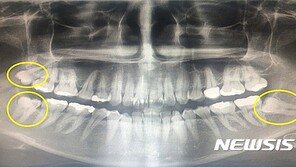

사랑니는 구강 내 맨 구석에서 가장 늦게 나오는 세 번째 큰 어금니다. 사람에 따라 평생 나지 않기도 하고, 4개 모두 나기도 있다. 사랑니는 정상적으로 나와 청결하게 유지할 수 있다면 어금니를 대체할 수도 있어 유용하지만 위치와 형태, 크기에 따라 발치가 필요한 경우도 있다. 특히 …